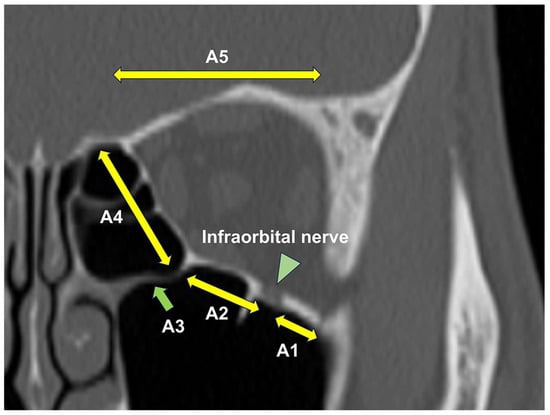

| Fracture Sites | |

| Single-wall fracture (including A1 + A2) | 297 |

| Multiple-wall fracture | 80 |

| Strut fracture | 23 |

| Orbital roof fracture | 3 |

| Trapdoor fracture | 144 |